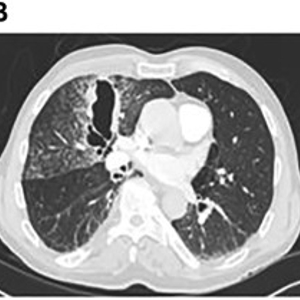

王大爷说那天医院CT太多人排队了没做上,去外院做的。今天带来了(图1)。

图1 三个月前王大爷的外院CT检查图像